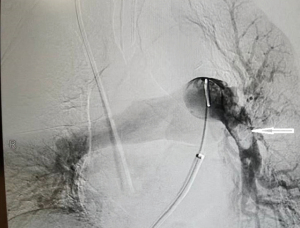

After 6 days of the support of ECMO and anticoagulation, the ECMO could not be weaned off, and TTE showed the persistent right atrial mass and severe pulmonary hypertension (Figure 1). In consideration of the ineffectiveness of ECMO support combined with anticoagulation, a discussion was held by the PERT; open-heart surgery was recommended, but the patient and his family members continued to refuse the open-heart surgery. On account of a previous report of successfully using of percutaneous thrombectomy to treat the right atrial mass, the patient and his family expressed willingness to receive the treatment of percutaneous thrombectomy (7). The patient was then referred to the digital subtraction angiography (DSA) room. During the angiography, no right atrial filling defect was found, and the intraoperative transthoracic echocardiogram confirmed the disappearance of the right atrial mass. Further pulmonary arteriography revealed embolisms in the main pulmonary arteries on both sides. There was a large round filling defect near the main pulmonary artery on the left main branch, and the exfoliated right atrial thrombus was considered (Figure 3). As the patient had a history of hypotension and elevated cardiac troponin I, a massive PE was diagnosed.

The AngioJet device was used to spray thrombolytics directly into the pulmonary arteries and entrain thrombi into the body of the catheter. However, sinus bradycardia and hypotension occurred when treating the main branches of the right pulmonary artery; so the AngioJet was withdrawn. After the heart rhythm and blood pressure were recovered, a 5-F pigtail catheter was rotated back and forth through the thrombus of the main branches of the right pulmonary artery except the right upper pulmonary artery branch (7).